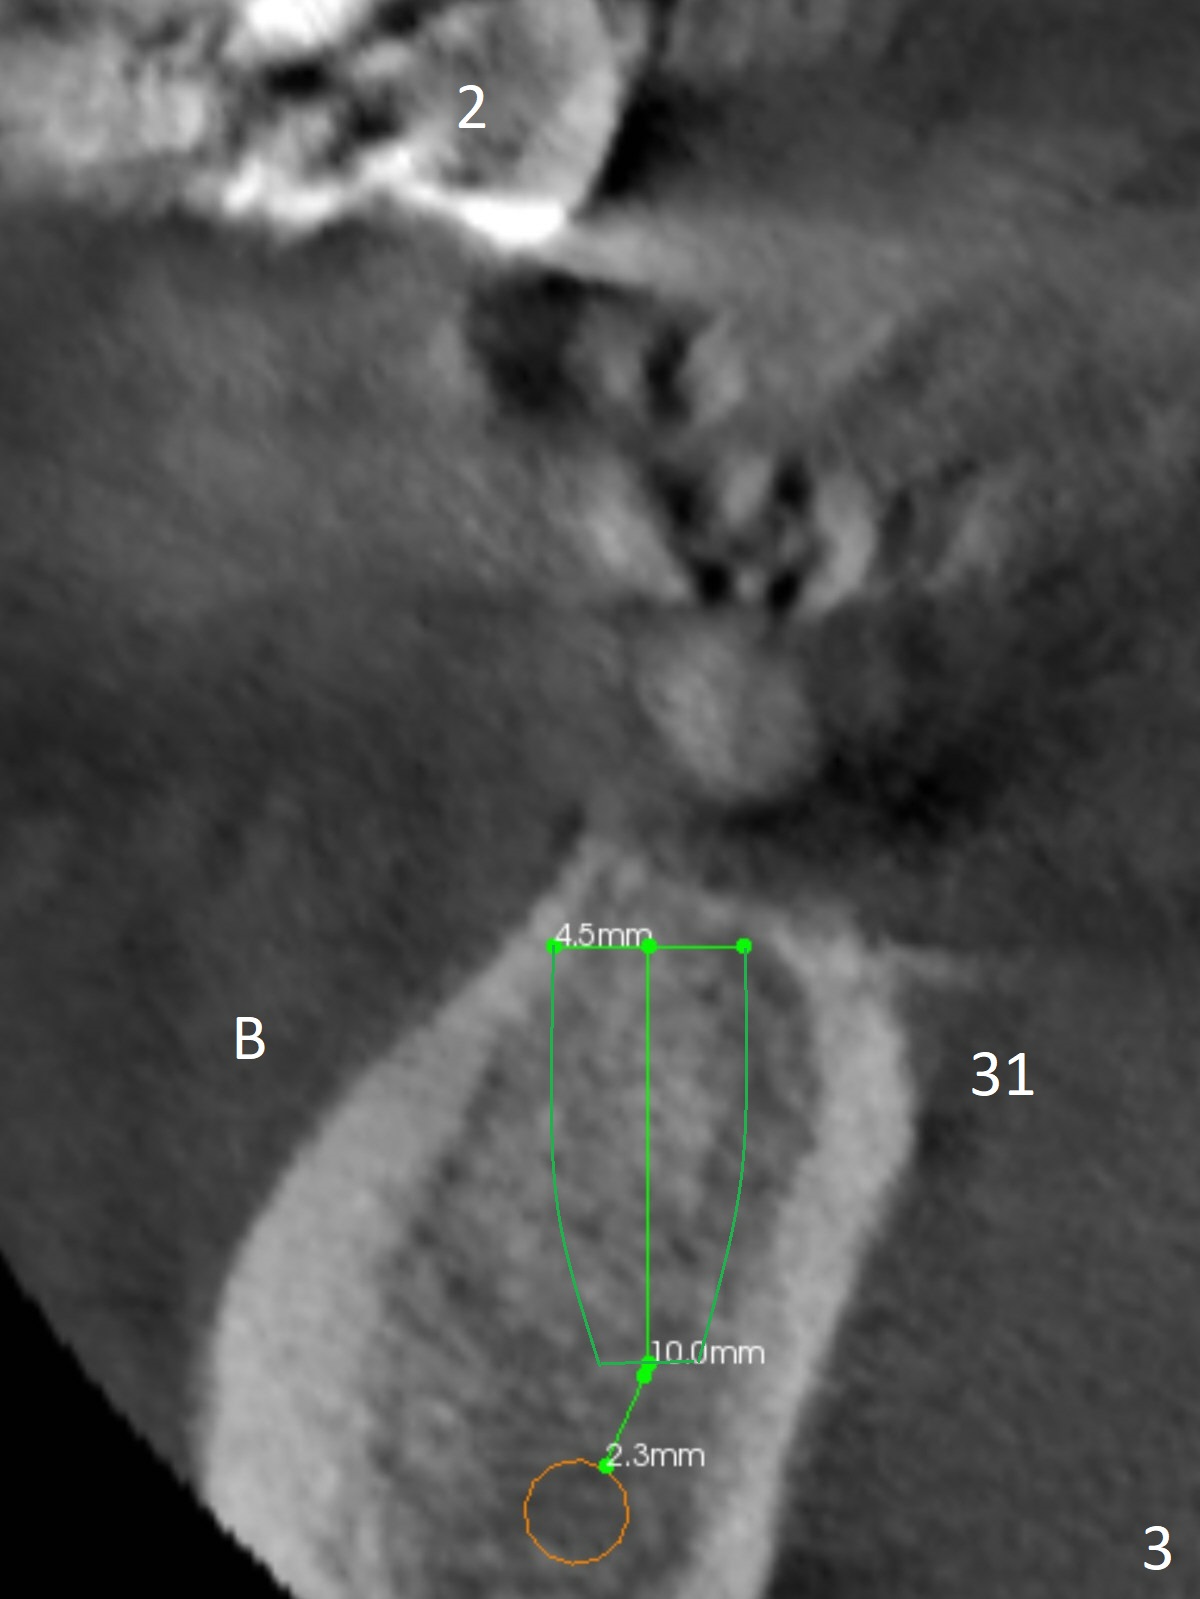

A healthy 37-year-old woman has 3 missing lower molars (Fig.1 panoramic view from CBCT). She has had implants at #8 and 10. The bone height for these molars is shown in Fig.2. The 1st molar ridges appear to be narrow (Fig.4,5,6), as compared to that of the 2nd molar (Fig.3 (B: buccal)). Ridge reduction seems to be necessary for the 1st molar sites prior to implant (green area) placement or deeper osteotomy.